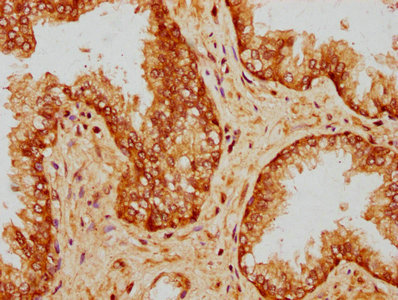

IHC image of CSB-PA018582LA01HU diluted at 1:200 and staining in paraffin-embedded human prostate cancer performed on a Leica BondTM system. After dewaxing and hydration, antigen retrieval was mediated by high pressure in a citrate buffer (pH 6.0). Section was blocked with 10% normal goat serum 30min at RT. Then primary antibody (1% BSA) was incubated at 4°C overnight. The primary is detected by a biotinylated secondary antibody and visualized using an HRP conjugated SP system.